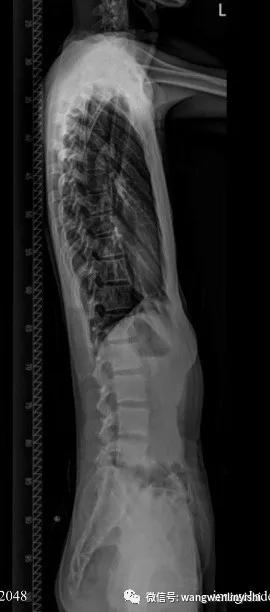

最近我们接诊了一位重度扁平胸患者。患者男性,20岁,前胸壁极度扁平,正常胸廓弧度消失。侧面看前后胸壁间距离明显缩短,且上下一致,脊柱生理弯曲消失,合并直背综合征。X线检查正位片提示胸廓较宽,肋骨水平;侧位片提示胸壁前后径缩短,胸骨与脊柱近似平行,生理弯曲消失,心脏和肺明显受压。

(X线侧位片)